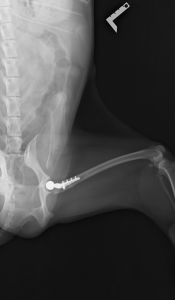

術後レントゲン画像

大腿骨が扁平な形をしていたため、予定していたインプラント(ステム)の厚みが合わず、大腿骨の髄腔内を削るなどの試行錯誤をしました。最終的に、体重強度の許容範囲内で1サイズ小さいインプラントを使用しました。